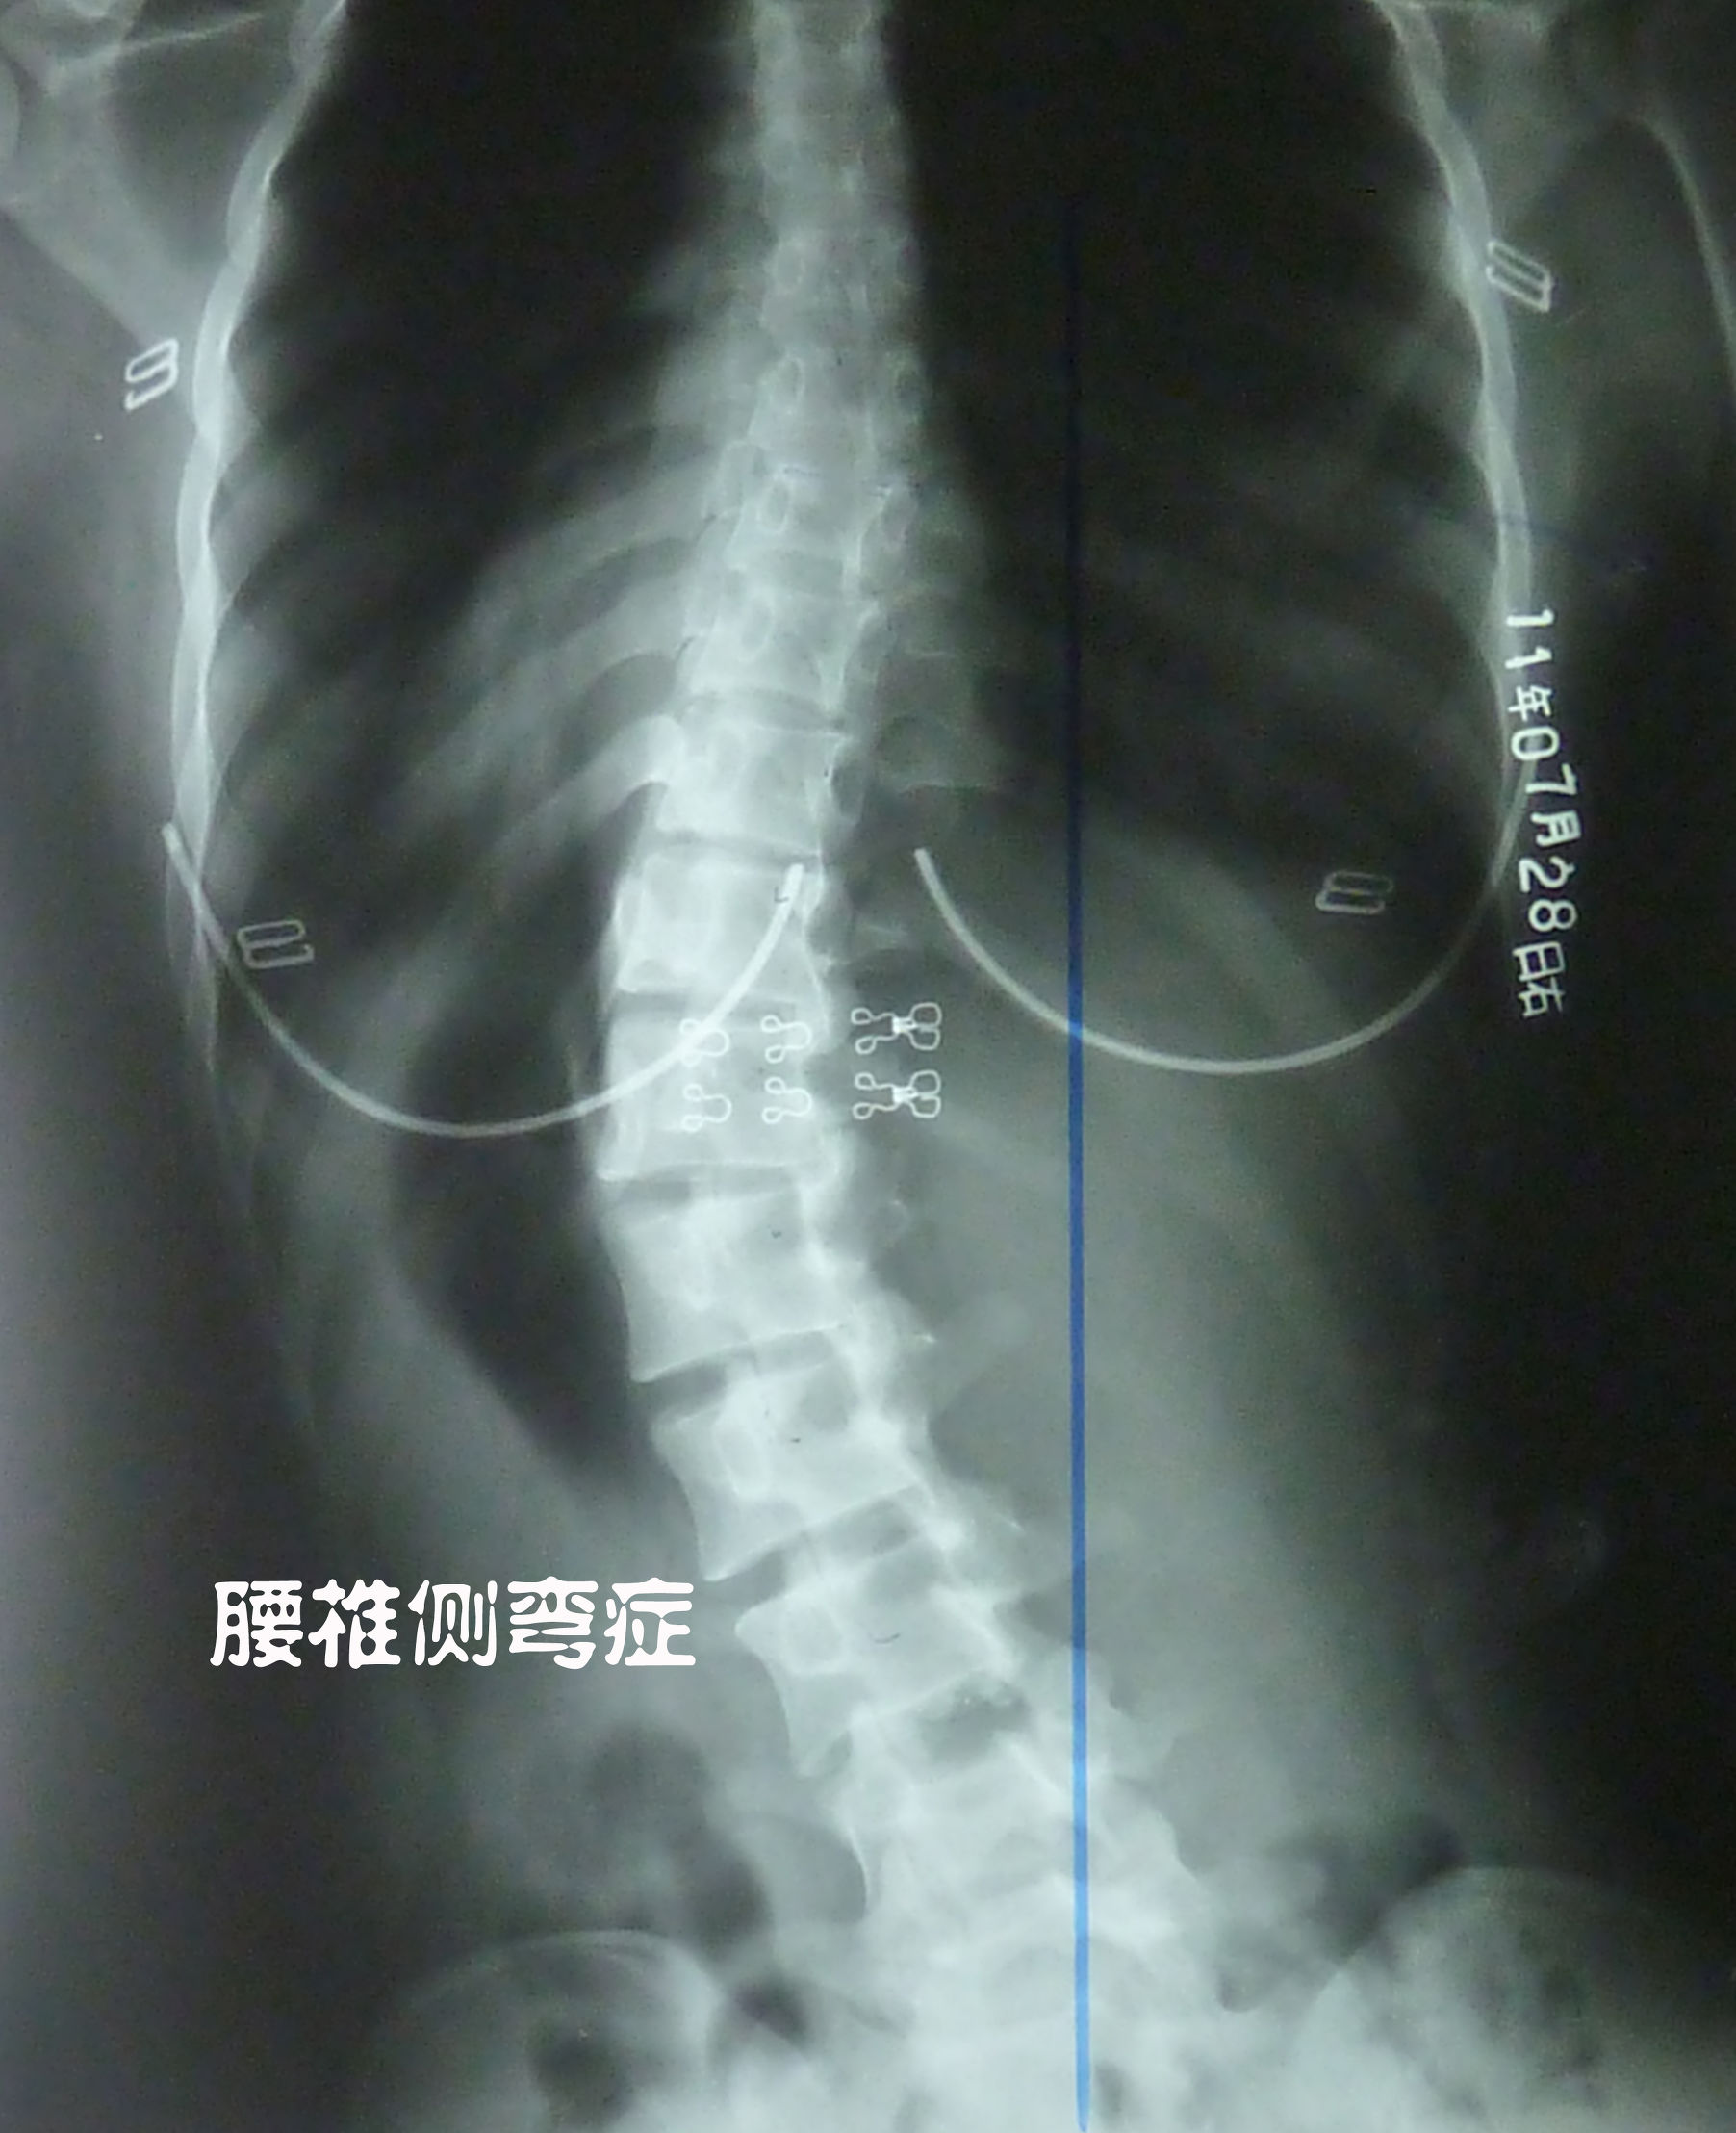

如下图所示:腰椎侧弯的人,一般都伴随腰椎间盘突出。

经临床研究发现,70%腰椎间盘突出的患者没有症状,说明这70%的患者根本没有压迫到神经,其中有一部分人仅表现为腰疼,而没有压迫神经腿麻的症状,但这并不是腰椎间盘突出所引起。引起腰疼的根本原因在于腰椎的变形和错位(比如有腰椎侧弯,椎体移位,腰椎反张,骨盆倾斜),从而导致脊柱生物力学失衡,腰椎受力不均匀,腰肌受牵拉而劳损 ,进而出现腰疼。而且 引起腰椎间盘突出的原因恰恰也是变形和错位。如果你的腰椎结构良好(曲度正常,没有侧弯,没有错位,没有骨盆倾斜),整个脊柱生物力学平衡,腰椎间盘受力均匀,就很难得腰椎间盘突出,除非受伤因素。